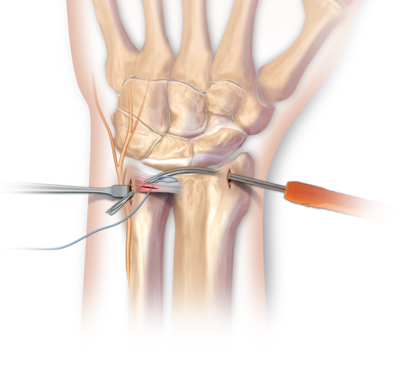

중심부파열(1A의 경우)은 원위 요척관절의 불안정성을 일으키지 않으므로, 고정과 항염증 약물 등의 보존적 방법으로 치료가 가능하지만, 파열 부위가 계속적인 통증을 일으킬 경우는 관절경적 변연절제술 을 시행할 수 있습니다.

변연부(1B, 1D)의 경우 혈행이 좋으므로 봉합하면 치유가 될 수 있는데,

1B의 경우 관절경을 이용하고 1D의 경우 개방적 봉합이 용이합니다.

정리해보면, 외상과 퇴행성 삼각섬유연골 치료는 위의 설명드린 것처럼 보존적 치료나, 수술 두가지로 나눠서 볼 수 있습니다. 신경 통증이 생기는 파열된 부분을 변열절제술 하는 방법이 가장 쉽고 흔하며 파열된 인대를 나사나, 실 등을 이용하여 봉합해주는 방법이 주로 사용되고 있습니다.